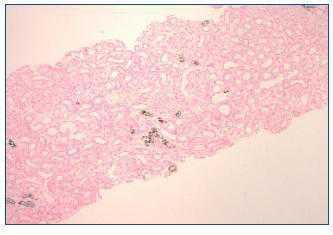

A week later, the patient reported pedal and orbital oedema and was observed on the emergency department. The physical examination was unremarkable except for hypertension (180/80 mmHg) and lower limbs oedema. Laboratory results showed haemoglobin 11.1 g/dl, serum urea 346 mg/dl, serum creatinine 9.2 mg/dl, serum sodium 130 mEq/L, serum potassium 6.5 mEq/L, serum phosphorus 6.6 mg/dl, normal serum calcium, serum bicarbonate 15 mEq/L and mild proteinuria. Serum and urine immunoelectrophoresis and immunologic study were normal. Renal ultrasound showed increased cortical echogenicity. Haemodialysis was initiated. Kidney biopsy showed minimal mesangial expansion. The tubules were mildly dilated and focal interstitial fibrosis was present. Von Kossa stain positive deposits were observed within the cytoplasm of tubular epithelial cells, tubular lumen and interstitium (figure 1 and figure 2). Immunofluorescence was negative for immunoglobulin or complement.

The second form is due to AphN with a more insidious onset (days to months) and is generally irreversible1. At the time of diagnosis, serum phosphorus and calcium levels are normal, unless measured within 3 days of bowel preparation. This was in fact the case of the first patient. As we found, the main pathologic finding in kidney biopsy is nephrocalcinosis demonstrated with the Von Kossa stain1.

Figure 2. Kidney biopsy. Von Kossa coloration (100x).